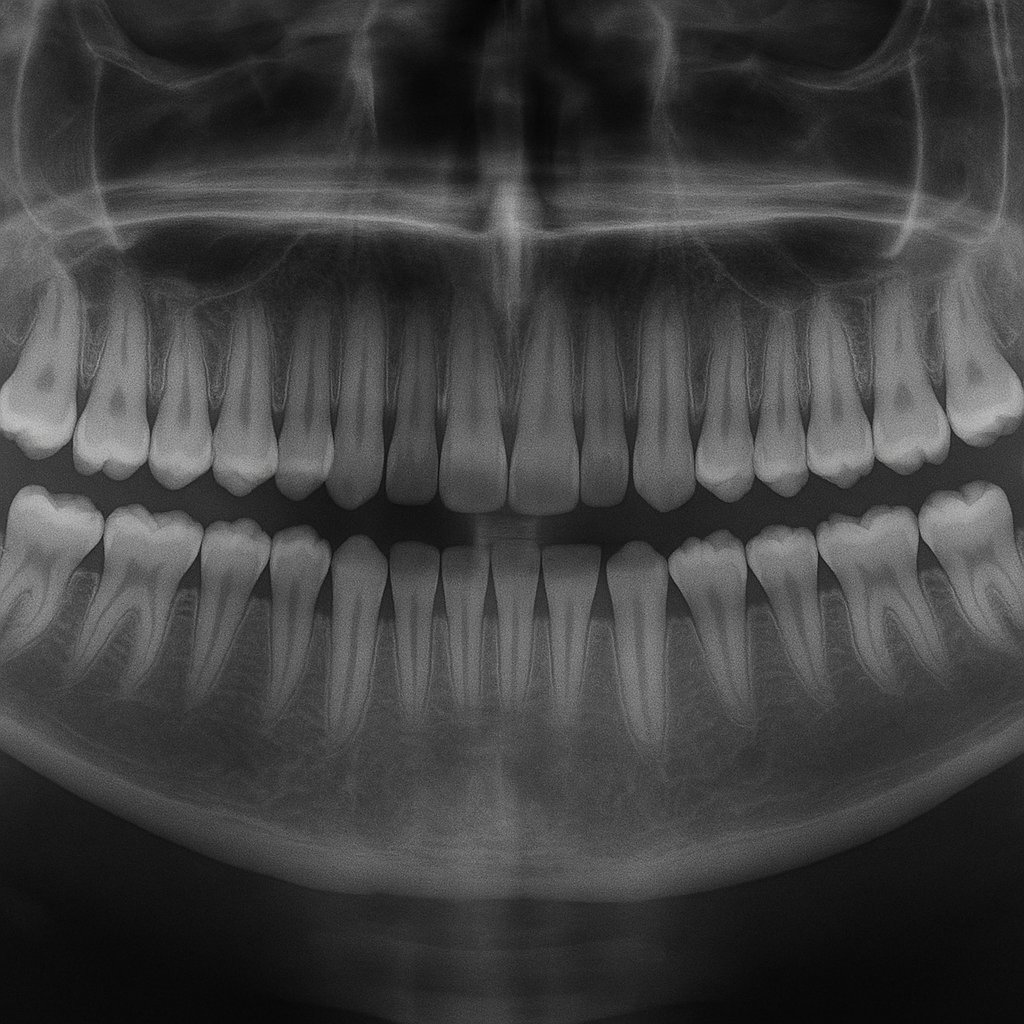

Zdjęcie panoramiczne zębów, nazywane również zdjęciem pantomograficznym lub pantomogramem, to rodzaj zdjęcia rentgenowskiego obejmującego całą jamę ustną w jednym ujęciu. W odróżnieniu od tradycyjnych zdjęć punktowych, które pokazują jedynie fragment uzębienia, panoramka prezentuje pełen obraz łuków zębowych, kości szczęk, żuchwy oraz sąsiadujących struktur. Dzięki temu stomatolog zyskuje szeroki, przekrojowy wgląd w sytuację w jamie ustnej, co w wielu przypadkach decyduje o prawidłowym rozpoznaniu problemu oraz wyborze optymalnego planu terapii.

Zdjęcie panoramiczne jest szczególnie przydatne, gdy pacjent pojawia się po raz pierwszy w gabinecie, nie znając dokładnie stanu swojego uzębienia. W jednej chwili można ocenić obecność ubytków, zębów niewyrzniętych, zatrzymanych, zębów nadliczbowych, zmian okołowierzchołkowych, torbieli czy innych nieprawidłowości. Daje to stomatologowi z Kliniki Stomatologicznej Artodonto kompletną bazę do planowania złożonego leczenia, zwłaszcza gdy obejmuje ono kilka dziedzin, takich jak endodoncja, protetyka, ortodoncja oraz chirurgia.

Zdjęcie panoramiczne zębów zajmuje szczególne miejsce w diagnostyce stomatologicznej. Jest badaniem pierwszego rzutu w wielu dziedzinach, ponieważ dostarcza przekrojowych informacji o stanie uzębienia i tkanek kostnych. W Klinice Stomatologicznej Artodonto w dzielnicy Warszawa Śródmieście pantomogram pełni funkcję mapy, na podstawie której planuje się kolejne etapy leczenia. Umożliwia wykrycie zmian, które jeszcze nie dają objawów bólowych, a które w przyszłości mogłyby spowodować poważniejsze problemy zdrowotne.

W leczeniu zachowawczym zdjęcie panoramiczne pomaga wykryć ukryte ubytki próchnicowe, zwłaszcza w trudnodostępnych miejscach, takich jak przestrzenie międzyzębowe czy okolice poniżej linii dziąseł. Pozwala też ocenić jakość wcześniejszych wypełnień oraz stan tkanek okołowierzchołkowych. Dzięki temu lekarz może precyzyjniej zaplanować leczenie kanałowe, określając długość i przebieg kanałów korzeniowych. W Artodonto, położonej w centrum Warszawy, takie zintegrowane podejście do diagnostyki i leczenia sprawia, że każda decyzja terapeutyczna opiera się na solidnych podstawach obrazowych.

Dla ortodontów pracujących w Klinice Stomatologicznej Artodonto zdjęcie panoramiczne jest narzędziem niezbędnym przy planowaniu leczenia wad zgryzu. Ukazuje położenie zawiązków zębów stałych, obecność zębów zatrzymanych, nadliczbowych, a także stopień rozwoju korzeni. Na podstawie takich informacji można przewidzieć, jakie zmiany nastąpią w przyszłości, oraz zaplanować odpowiedni aparat ortodontyczny czy ewentualne zabiegi chirurgiczne. Pacjenci z Warszawa Centrum, którzy rozważają rozpoczęcie terapii ortodontycznej, często właśnie od pantomogramu rozpoczynają swoją drogę do równych i funkcjonalnych łuków zębowych.

Równie istotna jest rola zdjęcia panoramicznego w chirurgii stomatologicznej i implantologii. Zabiegi usuwania zębów mądrości, resekcje wierzchołków korzeni, leczenie torbieli, a także wszczepianie implantów wymagają bardzo precyzyjnej analizy warunków anatomicznych. Pantomogram pozwala ocenić położenie korzeni względem struktur sąsiadujących, takich jak kanał żuchwowy czy dno zatoki szczękowej, co ogranicza ryzyko powikłań. W Artodonto w Warszawa Śródmieście badanie panoramiczne często stanowi etap wstępny, po którym w razie potrzeby uzupełnia się diagnostykę o tomografię komputerową, uzyskując trójwymiarowy obraz pola zabiegowego.

Nie można też pominąć znaczenia pantomogramu w diagnostyce chorób przyzębia. Pacjenci zgłaszający się do Kliniki Stomatologicznej Artodonto z objawami takimi jak krwawienie dziąseł, nieprzyjemny zapach z ust czy ruchomość zębów, w wielu przypadkach wymagają oceny poziomu kości wyrostków zębodołowych. Zdjęcie panoramiczne umożliwia zobrazowanie stopnia utraty kości, a tym samym pozwala na ocenę zaawansowania periodontopatii. Jest to podstawa do zaplanowania leczenia periodontologicznego, zabiegów regeneracyjnych oraz monitorowania efektów terapii w kolejnych latach.

W lokalizacji Warszawa Centrum wielu pacjentów prowadzi intensywny tryb życia, co wiąże się ze stresem, niekiedy ze zgrzytaniem zębów (bruksizmem) czy nieprawidłową pracą stawów skroniowo‑żuchwowych. Zdjęcie panoramiczne jest pomocne również w diagnostyce tego typu zaburzeń. Umożliwia ocenę struktury kostnej stawów, położenia głów żuchwy, a także ewentualnych zmian pourazowych. W połączeniu z badaniem klinicznym, wywiadem oraz dodatkowymi testami stanowi ważny element kompleksowej oceny narządu żucia.

Zdjęcie panoramiczne zębów służy również jako punkt odniesienia podczas monitorowania postępów terapii. Po zakończeniu leczenia kanałowego lekarz może ocenić na kolejnym zdjęciu, czy tkanki okołowierzchołkowe prawidłowo się wygoiły. Po zabiegu implantologicznym pantomogram pozwala sprawdzić pozycję wszczepów oraz integrację z kością. W ortodoncji porównanie zdjęć wykonanych przed i po leczeniu umożliwia ocenę uzyskanego efektu, a w periodontologii – stopnia zatrzymania lub spowolnienia zaniku kości. Dla pacjenta jest to czytelna forma wizualizacji rezultatów, która wzmacnia poczucie sensu podjętego leczenia.

Zdjęcie panoramiczne zębów pozwala wykryć wiele istotnych problemów, często zanim pojawi się ból lub inne wyraźne objawy. Na jednym obrazie lekarz widzi ubytki próchnicowe, zmiany okołowierzchołkowe, torbiele, zęby zatrzymane, nadliczbowe oraz nieprawidłowości w obrębie kości szczęk i żuchwy. Pantomogram jest także nieoceniony w diagnostyce chorób przyzębia, ponieważ ukazuje stopień zaniku kości wokół korzeni zębów. W Klinice Stomatologicznej Artodonto w dzielnicy Warszawa Śródmieście wynik badania stanowi punkt wyjścia do planowania leczenia zachowawczego, chirurgicznego, ortodontycznego czy implantologicznego.